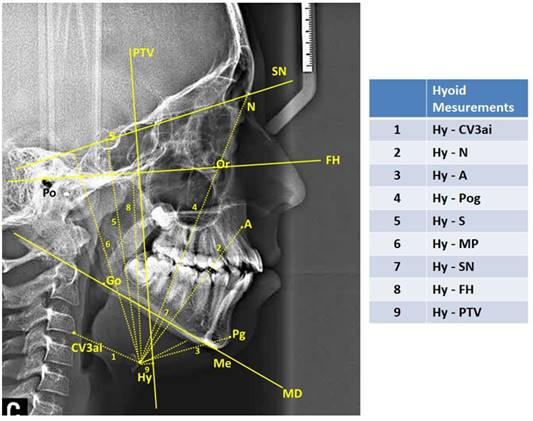

Lateral cephalometric films included in the study were calibrated on the Planmeca Romexis (Planmeca Romexis Viewer®, Helsinki, Finland) software program and were printed on tracing paper in 1:1 dimension in real size. Then, measurements were made by drawing the following cephalometric points and planes with the help of a 0.3 mm lead pencil. The cephalometric landmarks used in the study are shown in Figure 1, pharyngeal airway measurements in Figure 2, and hyoid measurements in Figure 3.

Area measurements were performed on digital lateral cephalometric films after digital calibration was performed in SketchAndCalc™ software program (SketchAndCalc Area Calculator software, Axiom Welldone ©, https://www.sketchandcalc.com/ . Area measurements are shown in Figure 3.

Figure 3

| Figure 3 Hyoid Measurements |

A statistically significant difference was found in all three groups divided according to growth and development periods in all of the hyoid measurements, except for the Hy - PTV (mm) measurement, which we evaluated the position of the hyoid bone, where we evaluated the position of the hyoid bone in the sagittal plane (p<0.05).

Finally, when the area measurements were examined, a statistically significant difference was found in all area measurements (oropharynx area, nasopharyngeal area, hypopharyngeal area) of the structures forming the airway in three groups divided according to growth and development periods (p<0.05) Table 2.